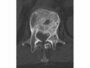

例えばCT写真(写真1)にあるように、腰骨(白い部分)には近くに脊髄があります。そのため、脊髄にできるだけ放射線が当たらないように、いろいろな方向からピンポイント照射することが可能になりました。その結果、転移も治癒できるようになってきているのが、(写真2)で示した最近の高精度放射線治療です。自分のがんが転移をしている場合、医師にこのような放射線治療ができないか確認してみてもよいでしょう。